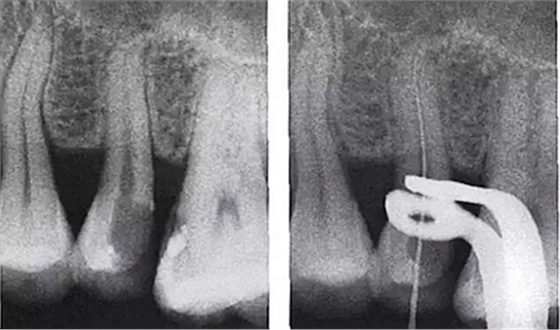

3.根管內(nèi)出現(xiàn)明顯的側(cè)支根管時。

解決:會通過側(cè)枝根管形成短路,當(dāng)銼針到達(dá)側(cè)枝根管口試即提示到達(dá)或超出根尖。

需結(jié)合X光片共同確認(rèn)!

5.用X線片輔助確認(rèn)

1.進(jìn)入側(cè)枝根管